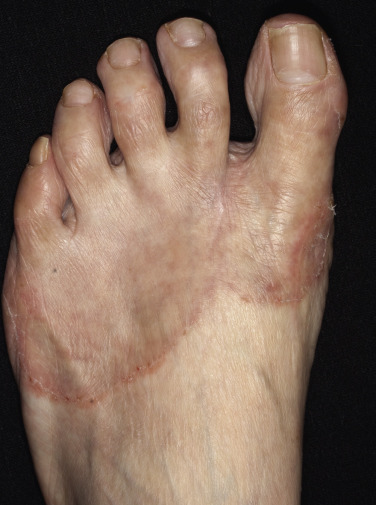

Tinea of the feet may present with the classic “ringworm” pattern ( Fig. 13.6 ), but most infections are found in the toe webs or on the soles.

Tight-fitting shoes compress the toes, creating a warm, moist environment in the toe webs; this environment is suited to fungal growth. The web between the fourth and fifth toes is most commonly involved, but all webs may be infected. The area between the fourth and fifth toes is subject to friction between the bones of the metatarsal and phalanx, resulting in callous formation (soft corn). After adequate treatment for fungus, the callus may still remain and should be mechanically removed to prevent further infection. The web can become dry, scaly, and fissured or white, macerated, and soggy ( Fig. 13.7 ). Itching is most intense when the shoes and socks are removed. The bacterial flora is unchanged when the tinea-infected webs demonstrate scale and peeling without maceration. Overgrowth of the resident bacterial population determines the severity of interdigital toe web infection. The macerated pattern of infection occurs from an interaction of bacteria and fungus. Dermatophytes initiate the damage to the stratum corneum and, by the production of antibiotics, influence the selection of a more antibiotic-resistant bacterial population. The prevalence of Staphylococcus aureus, Gram-negative bacteria, Corynebacterium minutissimum, Staphylococcus epidermidis, and Micrococcus sedentarius increases. Extension out of the web space onto the plantar surface or the dorsum of the foot is common and occurs with the typical, chronic, ringworm type of scaly, advancing border or with an acute, vesicular eruption ( Fig. 13.8 ). Identification of fungal hyphae in the macerated skin of the toe webs may be difficult.